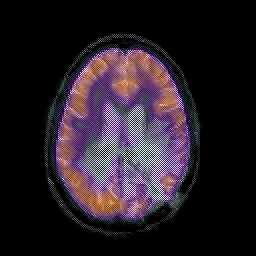

Glioblastoma multiforme overlay -- Slice #34

[Home][Help][Clinical][Tour 1][Tour 2][Tour 3] Slice 34